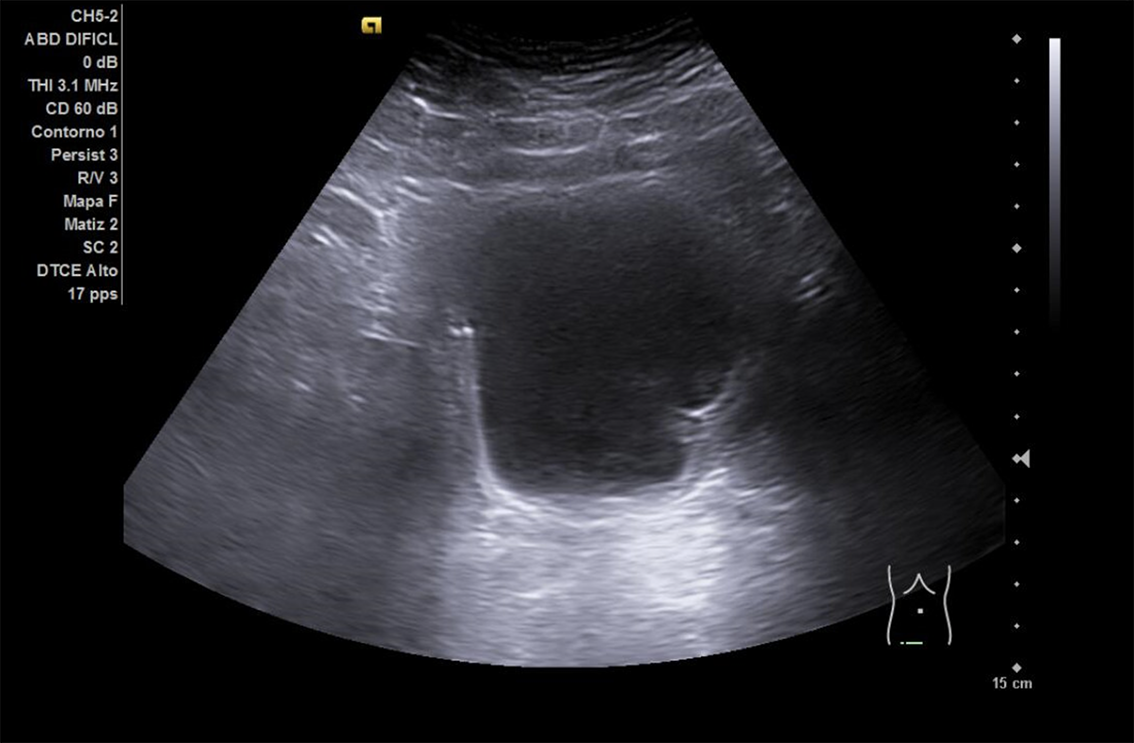

Se realiza ECO POCUS en la que se aprecia riñón derecho de morfología y tamaño normal. Riñón izquierdo con hidronefrosis grado III. A nivel de vejiga, bien replecionada se aprecia masa a nivel de pared izquierda adyacente a unión ureterovesical de 1.8 x 2,7 cm Ausencia de jet izquierdo.